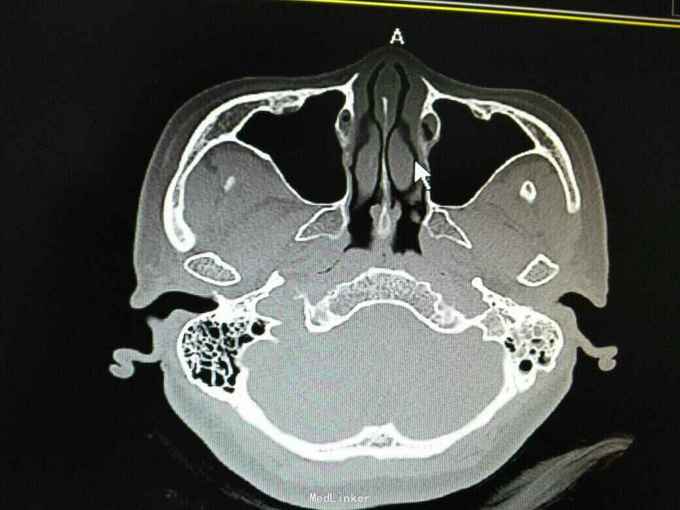

外耳道胆脂瘤,并 分泌性中耳炎? 胆固醇肉芽肿?

患者女性,47岁,以听力下降一周为主诉入院。 就诊后见外耳道后壁缺损,鼓室內积液,给予抗炎治疗后,鼓室內积液由缺损外耳道排出,呈棕褐色。 辅助检查:纯音听阈基本无听力损失。 诊断 外耳道胆脂瘤,并 分泌性中耳炎? 胆固醇肉芽肿? 治疗: 1.乳突根治术?乳突蜂房气化非常好,比较难做。 2.外耳道成型、后壁修补?